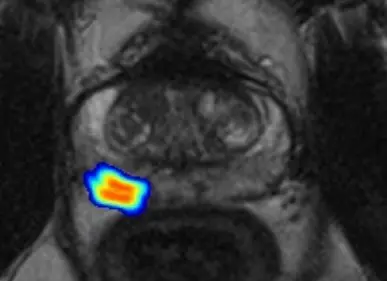

If a PSA test shows an elevated value, this may be an indicator of prostate cancer. To confirm this suspicion, doctors today first order magnetic resonance (MR) imaging as a further diagnostic test. The “multiparametric MRI“ used here combines various imaging techniques and therefore provides very detailed images.

An algorithm developed at the DKFZ for evaluating image data was trained with the MRI images of over 1000 of these men. Using the remaining 500 or so data sets, the researchers tested whether a combination of their risk calculator with the AI could improve the accuracy of prostate cancer prediction.

If the PI-RADS value in the risk calculator was replaced by the AI method, the diagnostic significance hardly changed. In contrast, the combination of AI and PI-RADS delivered significantly better results: It identified 49 percent as minimal risk among men who had originally been biopsied. “This means that the combination of deep learning and radiological findings could theoretically have avoided almost half of these biopsies without overlooking a relevant number of tumors,“ says Adrian Schrader from the DKFZ, first author of the current study.